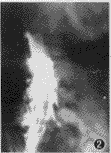

图2 显示造影柱阻塞端向后移位 9 mm